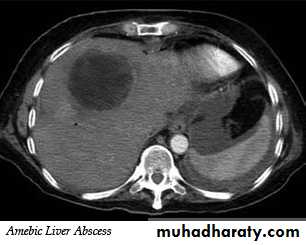

They are the commonest benign tumors in liver. They are common incidental finding and rarely requires treatment. It may cause significant hemorrhage, especially after trauma ,so percutaneous biopsy should be avoided. Hemangiomas are typically well-defined, peripheral echogenic masses at US. At CT, there is usually a characteristic peripheral, nodular and centripetal enhancement after IV contrast. MRI shows uniform very high signal intensity on T2 images.Liver abscess

It appears similar to cysts but have a thick irregular wall with fluid center.

Occasionally chronic abscess calcify.

It cannot be distinguished from necrotic tumor , but the clinical events should aid in the diagnosis. Aspiration under US guidance is invariably undertaken.